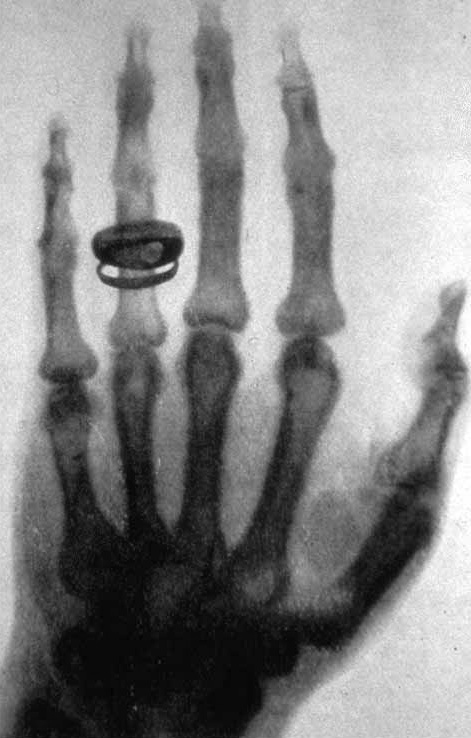

Om du någon gång tagit en röntgenbild, till exempel hos tandläkaren eller om du brutit armen, så har du träffat på joniserande strålning. Du har säkert också hört talas om kärnkraftverk och den debatt som finns kring detta. Radioaktivitet och strålning kan verka skrämmande. Vi vet att vi kan få obotliga skador och cancer om vi utsätts för stark strålning. Samtidigt kan strålning användas för att rädda liv, bland annat vid cancerbehandling. Radioaktivitet är när vissa, instabila atomkärnor omvandlas till stabila atomkärnor utan någon yttre påverkan. Den energi som frigörs vid denna omvandling skickas ut som strålning. Strålningens energi är så hög att den kan jonisera material som absorberar strålningen. Med jonisering menas att det bildas joner. Strålningen kallas därför joniserande strålning. Vi har känt till joniserande strålning sedan slutet av 1800-taletÅr 1895 upptäckte Wilhelm Röntgen en ny typ av strålning som bildades vid elektriska urladdningar i ett glasrör under vakuum. Strålningen kunde tränga igenom material som vanligt ljus inte kunde gå igenom. Röntgen kallade strålningen för X-strålning och det heter den fortfarande på engelska (X-rays). Röntgenstrålning kallas ofta för den viktigaste upptäckten inom medicinen och Röntgen fick det allra första nobelpriset i fysik, år 1901. Ungefär samtidigt upptäckte Henri Becquerel att salter av grundämnet uran gjorde fotografiska plåtar svarta. Fotografiska plåtar användes för att ta bilder i gamla tiders kameror. Uran skickar ut joniserande strålning som reagerar med den fotografiska plåten som då blir svart. Becquerel hade upptäckt radioaktiviteten och belönades med nobelpriset i fysik 1903. Upptäckterna av röntgenstrålning och radioaktivitet väckte intresse hos andra forskare och snart var det många som forskade om radioaktivitet och joniserande strålning. Under de första 11 år som nobelpris i fysik och kemi delades ut var sex av pristagarna personer som forskade inom joniserande strålning och radioaktivitet. En av forskarna, Marie Curie, belönades med nobelpris i både fysik och kemi under denna period.

Ett annat användningsområde är att använda strålningen för att undersöka material. Ett exempel är en röntgenundersökning. Material med olika densitet absorberar olika mycket strålning. Om vi bestrålar en arm med röntgenstrålning och har en fotografisk plåt på andra sidan armen går mindre strålning genom själva skelettet än genom den mjuka vävnaden. Det ser därför ut som om vi fotograferar skelettet. Röntgenundersökningar används också i industrin, bland annat för att leta efter sprickor i metallkonstruktioner. Röntgenstrålning kan också användas för att få detaljerad information om strukturen hos material. Genom att studera hur röntgenstrålningen sprids är det möjligt att ta reda på hur atomerna i en kristall sitter. Det går också att bestämma avstånd mellan atomer. Dessa tekniker utvecklas snabbt och för de mest avancerade tillämpningarna behövs så kallat synkrotronljus.